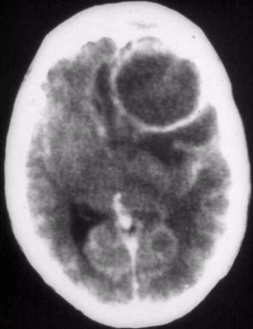

What are the consequences of a space occupying lesion in the brain?

- Herniation